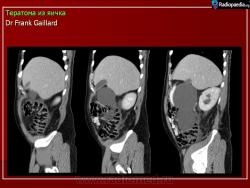

2.

Из литературных источников.